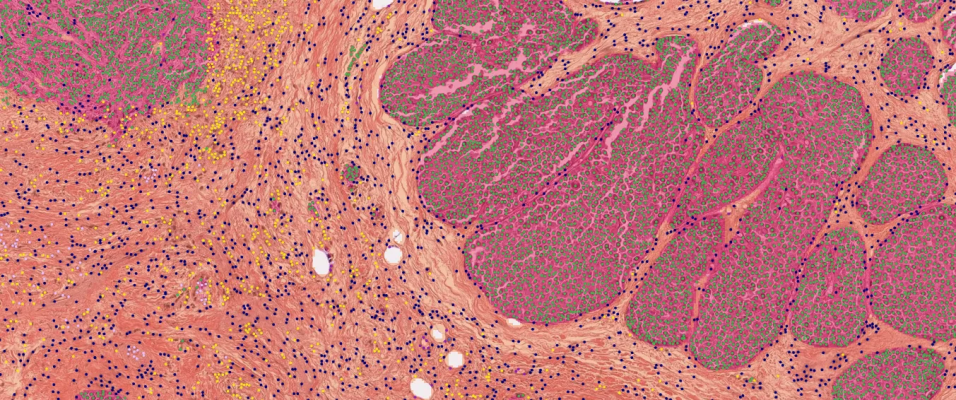

The company, a deep learning-based medical AI company developing AI solutions for precision diagnostics and treatment support, described that its SCOPE IO is an AI-powered H&E analyzer which identifies Tertiary Lymphoid Structures (TLS) within the tumor microenvironment (TME). It was developed with a dataset of thousands of Hematoxylin and Eosin (H&E) stained whole-slide images derived from 18 different types of cancer from patients around the world.